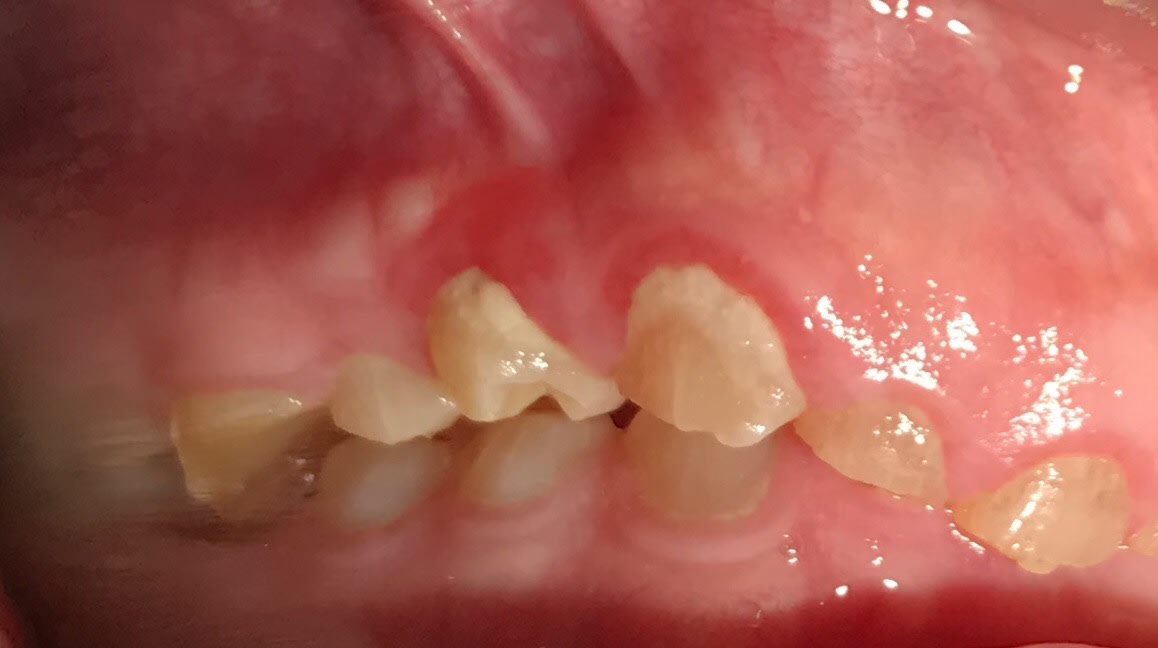

Bonjour je suis lenovo ici . Quelqu’un pourrait-il me donner toutes les étapes pour faire ce cas ? Que faut-il faire précisément ? Le patient n’a pas de contraintes financières. Pas de lésions apicales. Uniquement des usures de dents.

Je que je trouve impressionnant et peut être le plus complexe à gérer c'est cette bascule du pré maxillaire.

Les photos ne sont pas dingues, mais les usures semblent très majoritairement antérieures. Pourquoi?

Et le fait que 17 18 27 28 semblent intactes alors qu'apparemment il y a des antagonistes intactes aussi